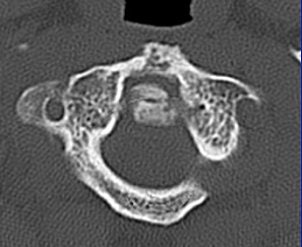

Whichever model is chosen, Cinnamon advised paying attention to the inverse relationship of contrast and spatial resolution, using the following case as an example (images F-G).

![]() |

| Image F |

"On the 2.5-mm slice, you can see the occipital condyle fracture. If (you) go down to the 0.5-mm slice, you can see the fracture just as well -- maybe it looks a little sharper. But you can still identify the fracture on the thicker slice. The value for this is on the coronal and sagittal reformatted images from the 2.5-mm axials. There's a tremendous amount of stair-step artifacts. On the 0.5-mm images, you've eliminated the stair-step artifact because your spatial resolution is so good."